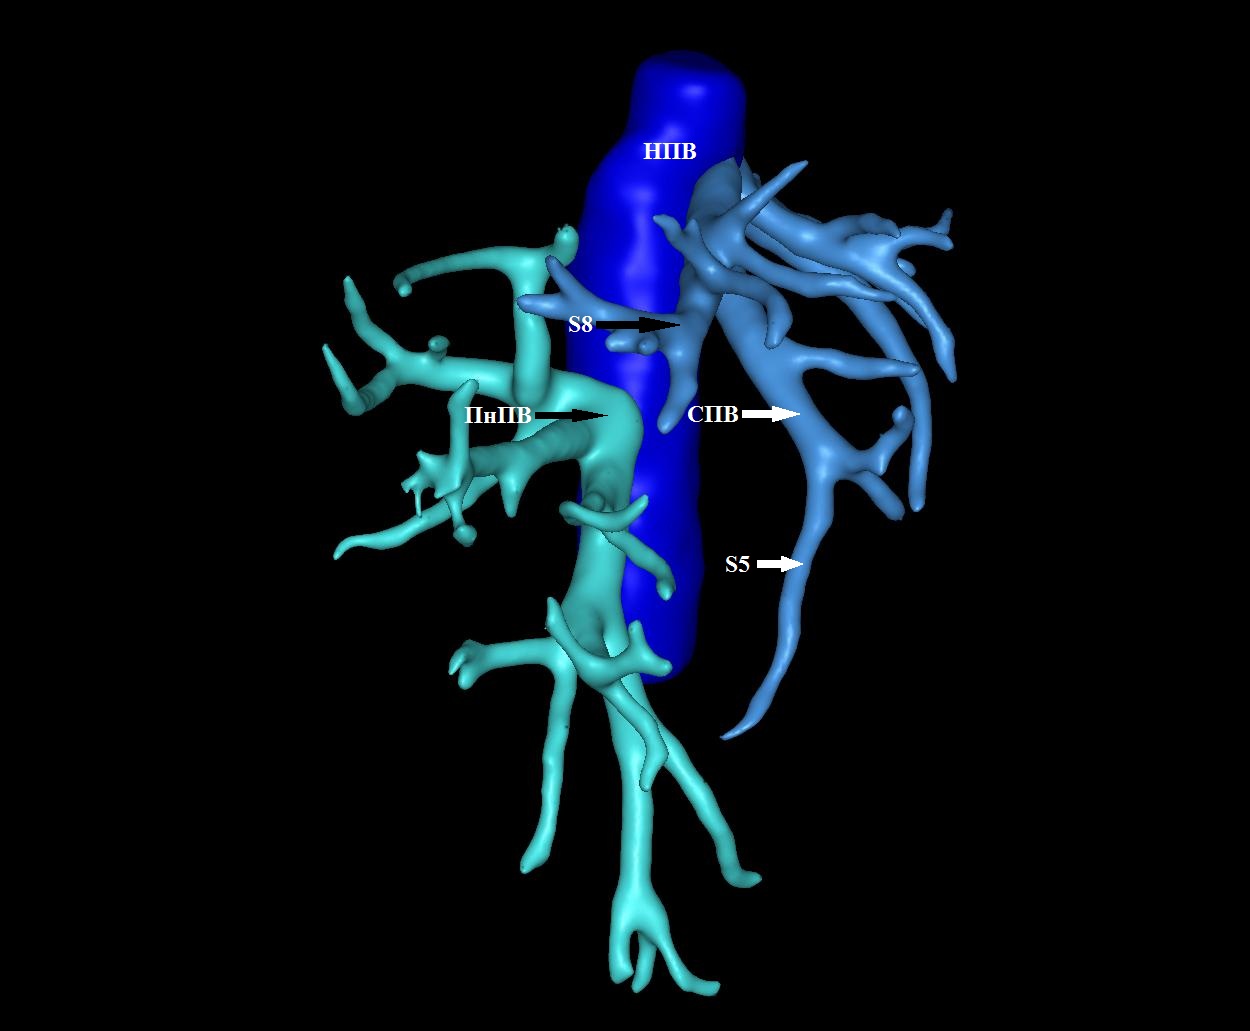

10. Тип С (фото). | |

| Тема | ||

| Тип | Исследовательские инструменты | |

Посмотреть

(2MB)

|

Метаданные ▾ | |